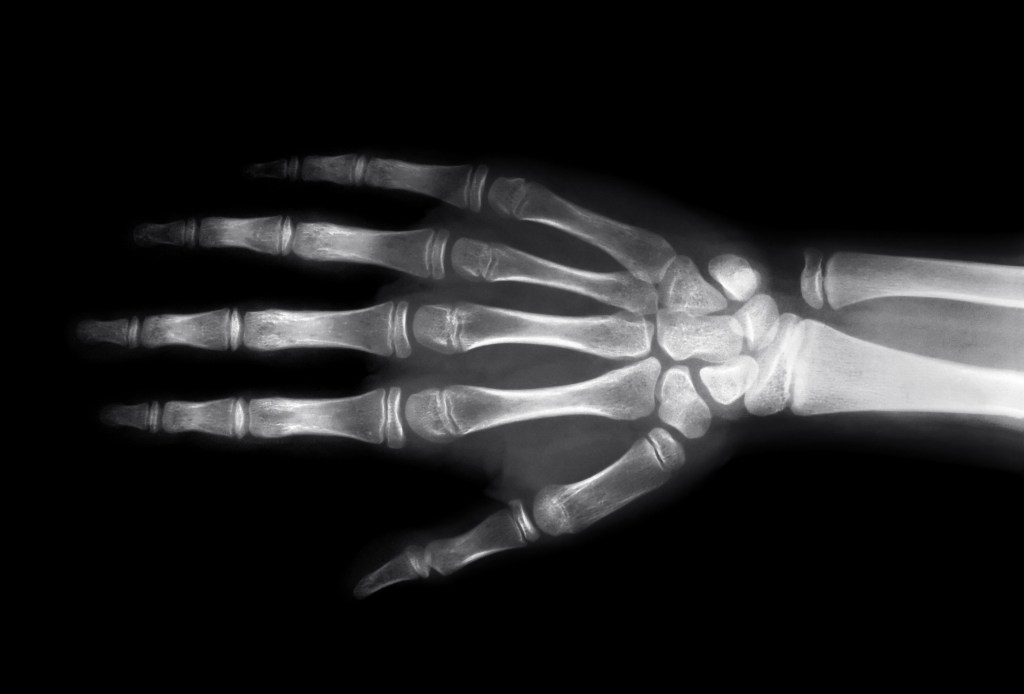

8 novembre 1895 – In quel giorno Wilhelm Conrad Röntgen scopre i “raggi X” (definiti così in quanto sconosciuti). Per testare le proprietà dei raggi il fisico tedesco utilizzò diversi oggetti, verificando ogni volta che questi ultimi risultavano trasparenti ai raggi, in modo da produrre un’immagine della loro struttura interna sulla lastra fotografica. Il test con la mano della moglie gli mostrò che anche il corpo umano era trasparente ai raggi, ad eccezione dello scheletro. La scoperta fu fondamentale per i successivi studi sulla radioattività e valse a Röntgen il Nobel per la Fisica nel 1901.